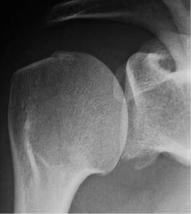

对关节盂骨缺损的评估:

通过正位X线看关节盂下方是否存在撕脱性骨折或者是轮廓的丢失。

正常

关节盂下缘撕脱性骨折

关节盂下缘轮廓丢失

如果正位X线上能看到关节盂下缘的轮廓丢失,则同样应为2分。